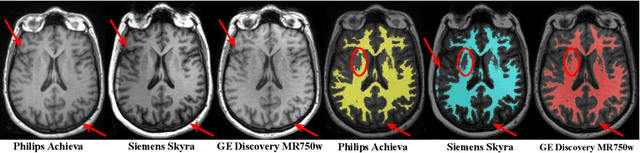

Abstract:Most publicly available brain MRI datasets are very homogeneous in terms of scanner and protocols, and it is difficult for models that learn from such data to generalize to multi-center and multi-scanner data. We propose a novel data augmentation approach with the aim of approximating the variability in terms of intensities and contrasts present in real world clinical data. We use a Gaussian Mixture Model based approach to change tissue intensities individually, producing new contrasts while preserving anatomical information. We train a deep learning model on a single scanner dataset and evaluate it on a multi-center and multi-scanner dataset. The proposed approach improves the generalization capability of the model to other scanners not present in the training data.